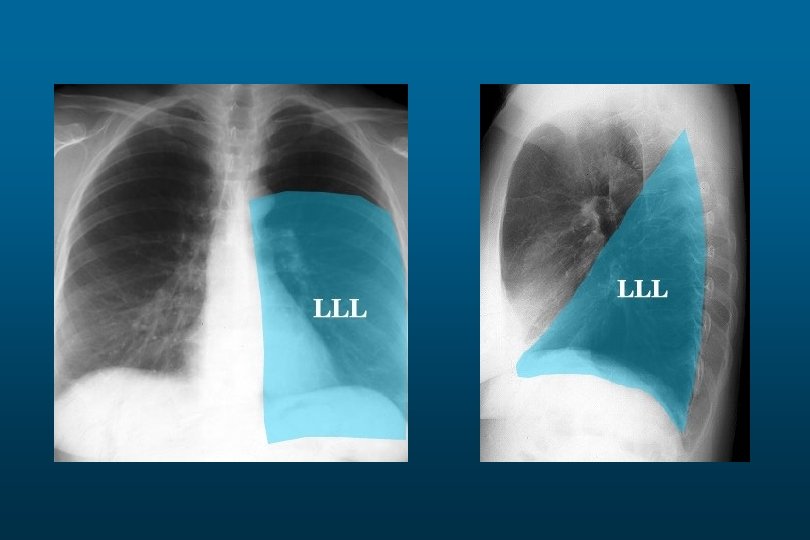

Left Lower Lobe Pneumonia